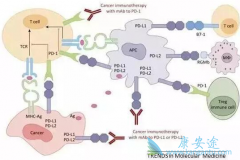

PD-1 抑制剂的诞生,确实为肿瘤医学的进步带来了巨大的跨越;它实现了横跨多个癌种的突破性进展;部分晚期患者实现了长期生存,可以说在现代抗肿瘤的拉锯战中取得了惊人的成绩,医学研究者们认为:免疫治疗将会是未来对抗癌症的主要方向之一。 那么 ...

在美国癌症领域顶级会议AACR年会上,来自中国的专家和数据第一次登上了主演讲台。以中国患者为主的关键、随机III期临床研究(CheckMate-078),首次证实了 PD-1 抑制剂在中国人群中的长期生存获益优势,其大获成功意味着nivolumab可能成为首个为中国晚期非 ...

最近几年, PD-1 抑制剂(PD-1抗体、PD-L1抗体)一路高歌猛进。截止到目前,PD-1抗体、PD-L1抗体、CTLA-4抗体等肿瘤免疫治疗新药,单独使用或者与其他治疗联合使用,已经被批准用于恶性黑色素瘤、非小细胞肺癌、胃癌、肝癌等所有微卫星高度不稳定的实体 ...

近年来,在肿瘤治疗领域最被寄予厚望的当属免疫疗法。肿瘤免疫治疗是利用人体的免疫机制,通过主动或被动的方法来增强患者免疫功能,达到杀伤肿瘤细胞的目的。医学界普遍认为,肿瘤免疫治疗在继手术、化疗、放疗、靶向治疗后将为肿瘤治疗领域带来一场全 ...